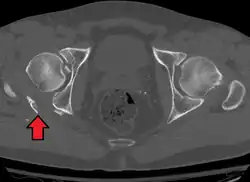

In all cases, CT scan can assist in identifying impacted bone pieces, which may be found within the joint, and MRI may be done to identify the extent of potential injury to the sciatic nerve.

Axial CT image (viewed on bone windows) of a complex comminuted left acetabular fracture involving both anterior and posterior columns. -

Fracture of the acetabulum